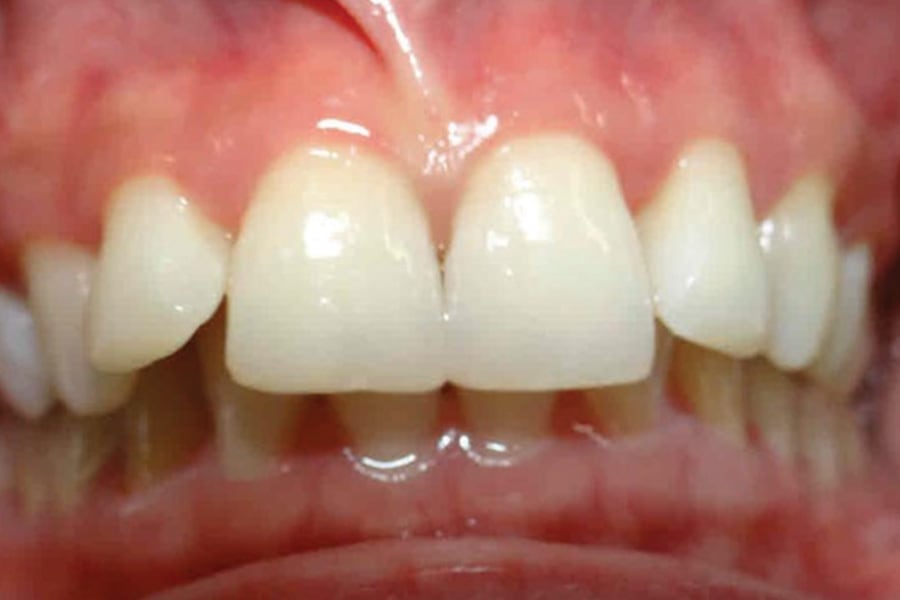

A 35-year-old woman presented with concerns of crowding, bruxism, and bite misalignment, which were associated with a class II malocclusion that would require a combination treatment of expansion, distalization, and molar derotation. ClearCorrect® aligner therapy (Straumann, clearcorrect.com) was selected as the primary modality, as the patient requested a non-invasive, esthetic treatment. The treatment plan was designed to be completed within 6 months of active aligner therapy. Class II elastics were prescribed, and the ClearCorrect FLEX case plan was chosen to allow for refinements, as needed. After comprehensive digital records were taken, the first set of aligners was delivered, engagers were bonded, and the patient was instructed to wear aligners on a 14-day cycle with full-time class II elastic wear. To enhance efficiency, more engagers were placed, including posterior attachments, to maximize control over molar distalization and anchorage. Interproximal reduction of 0.3 mm was performed in a few contacts at the initial appointment to facilitate space closure and alignment. Due to the complexity of the correction and the patient’s history of bruxism, a lower 3-3 bonded retainer was placed, and retainers were fabricated for both arches. The patient expressed a high level of satisfaction with the ClearCorrect aligner therapy, noting the comfort and esthetics of the aligners and the ability to achieve a fully corrected class II occlusion in just 6 months of treatment.